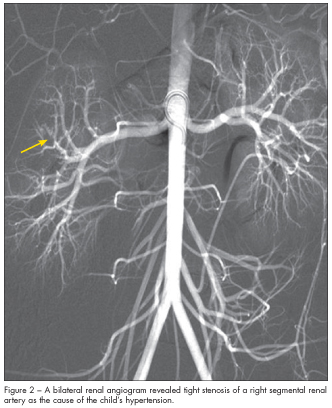

Renal Doppler ultrasonogram was normal. MRI scan of the brain revealed no intracranial pathology. However, while the patient was sedated for the MRI, automated blood pressures were 180/106 mm Hg and 177/110 mm Hg. This prompted an extensive evaluation for secondary hypertension. Results showed a plasma renin level of 4785 ng/dL and a serum aldosterone level of 89 ng/dL. A bilateral renal arteriogram revealed tight stenosis of a right segmental renal artery (Figure 2).